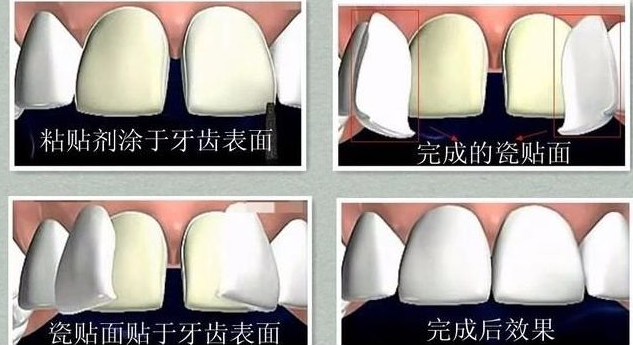

ЖдгкбРГнЬљУцЃЌвЛаЉХѓгбаФРяТѕВЛЙ§ШЅЕФПВОЭЪЧКІХТФЅбРЃЌЕЃаФФЅбРЛсЖдбРГнНЁПЕгаЮЃКІЁЃЯждкгаЕФПкЧЛвНдКв§НјСЫБЁПЩжС0.2КСУзЕФГЌБЁДЩЬљУцЃЌЬљУцЪаГЁЩЯвВгаВЛЩйаћДЋВЛФЅбРЬљУцЕФЁЃФЧУДЬљУцЧАБИбРЕНЕзгаУЛгаБивЊ?ЪЧВЛЪЧЫљгаШЫЖМПЩвдВЛФЅбРзіЬљУцФи?

бРЬљУц“ФЅбР”ЃЌЮвУЧдквНСЦЩЯГЦжЎЮЊ“БИбР”ЁЃЙЫУћЫМвхЃЌОЭЪЧжИдке§ЪНВйзїбРГнЬљУцжЎЧАЕФзМБИЙЄзїЃЌвдДяЕНБШНЯКУЕФЬљУцаЇЙћЁЃЦфЪЕЃЌЬљУцЧАЪЧЗёашвЊФЅбРжївЊШЁОігкЬљУцПЭШЫЕФПкФкбРГнЧщПігыУцаЭЁЃ

БШШчЫЕбРГнКЭУцаЭдБООЭНЯЭЙЕФПЭШЫЃЌВЛФЅбРжБНгЬљУцЃЌЮовЩЛсМгжиЭЙИаЃЛбРГнХХСаЪЎЗжНєУмЃЌСНВрУЛгазуЙЛВйзїПеМфЕФЛАПЩФмвВЛсашвЊЬсЧАдЄБИГівЛЕубРЗьЯЖ……

УцаЭКЭбРГнЖМВЛДцдкЭтЭЙЧщПіЃЌВЂЧвбРГнХХСаећЦыжЛЪЧНтОібРГнаЁЗьЯЖЮЪЬтЕФЛАЃЌКмДѓМИТЪЪЧПЩвдВЛФЅбРНјааЬљУцВйзїЕФЁЃЁЗЁЗЁЗЭЦМідФЖСЃКбРГнКмживЊЃЌетМИИіЪТЧщвЊжЊЕРЃЁ

КмУїЯдЃЌетИіАИР§дкДЩЬљУцаоИДЧАЛљБОЩЯЪЧВЛашвЊБИбРЕФЃЌЫљвдЪЧЗёФЅбРвВвЊШЁОігкФњЕФжїЫпЃЌШчЙћЪЧбРГнБОЩэбеЩЋКмЩюЃЌЯЃЭћПЩвдУРАзбРГнЕФЧщПіЃЌФЧБИбРСППЩФмЯрЖдОЭвЊЖрвЛаЉЁЃ

ДѓМвЖМЯЃЭћздМКПЩвдВЛФЅбРжБНгзіЬљУцЃЌЕЋЪЧЮвУЧвЊжЊЕРВЂВЛЪЧШЫШЫЖМЪЪКЯетжжЗНЪНЕФЁЃПМТЧзібРЬљУцЕФХѓгбУЧгІИУзіКУаФРэзМБИЃЌЕНзЈвЕПкЧЛЛњЙЙУцеязЈвЕУРбЇаоИДвНЩњдйзіОіЖЈЁЃ